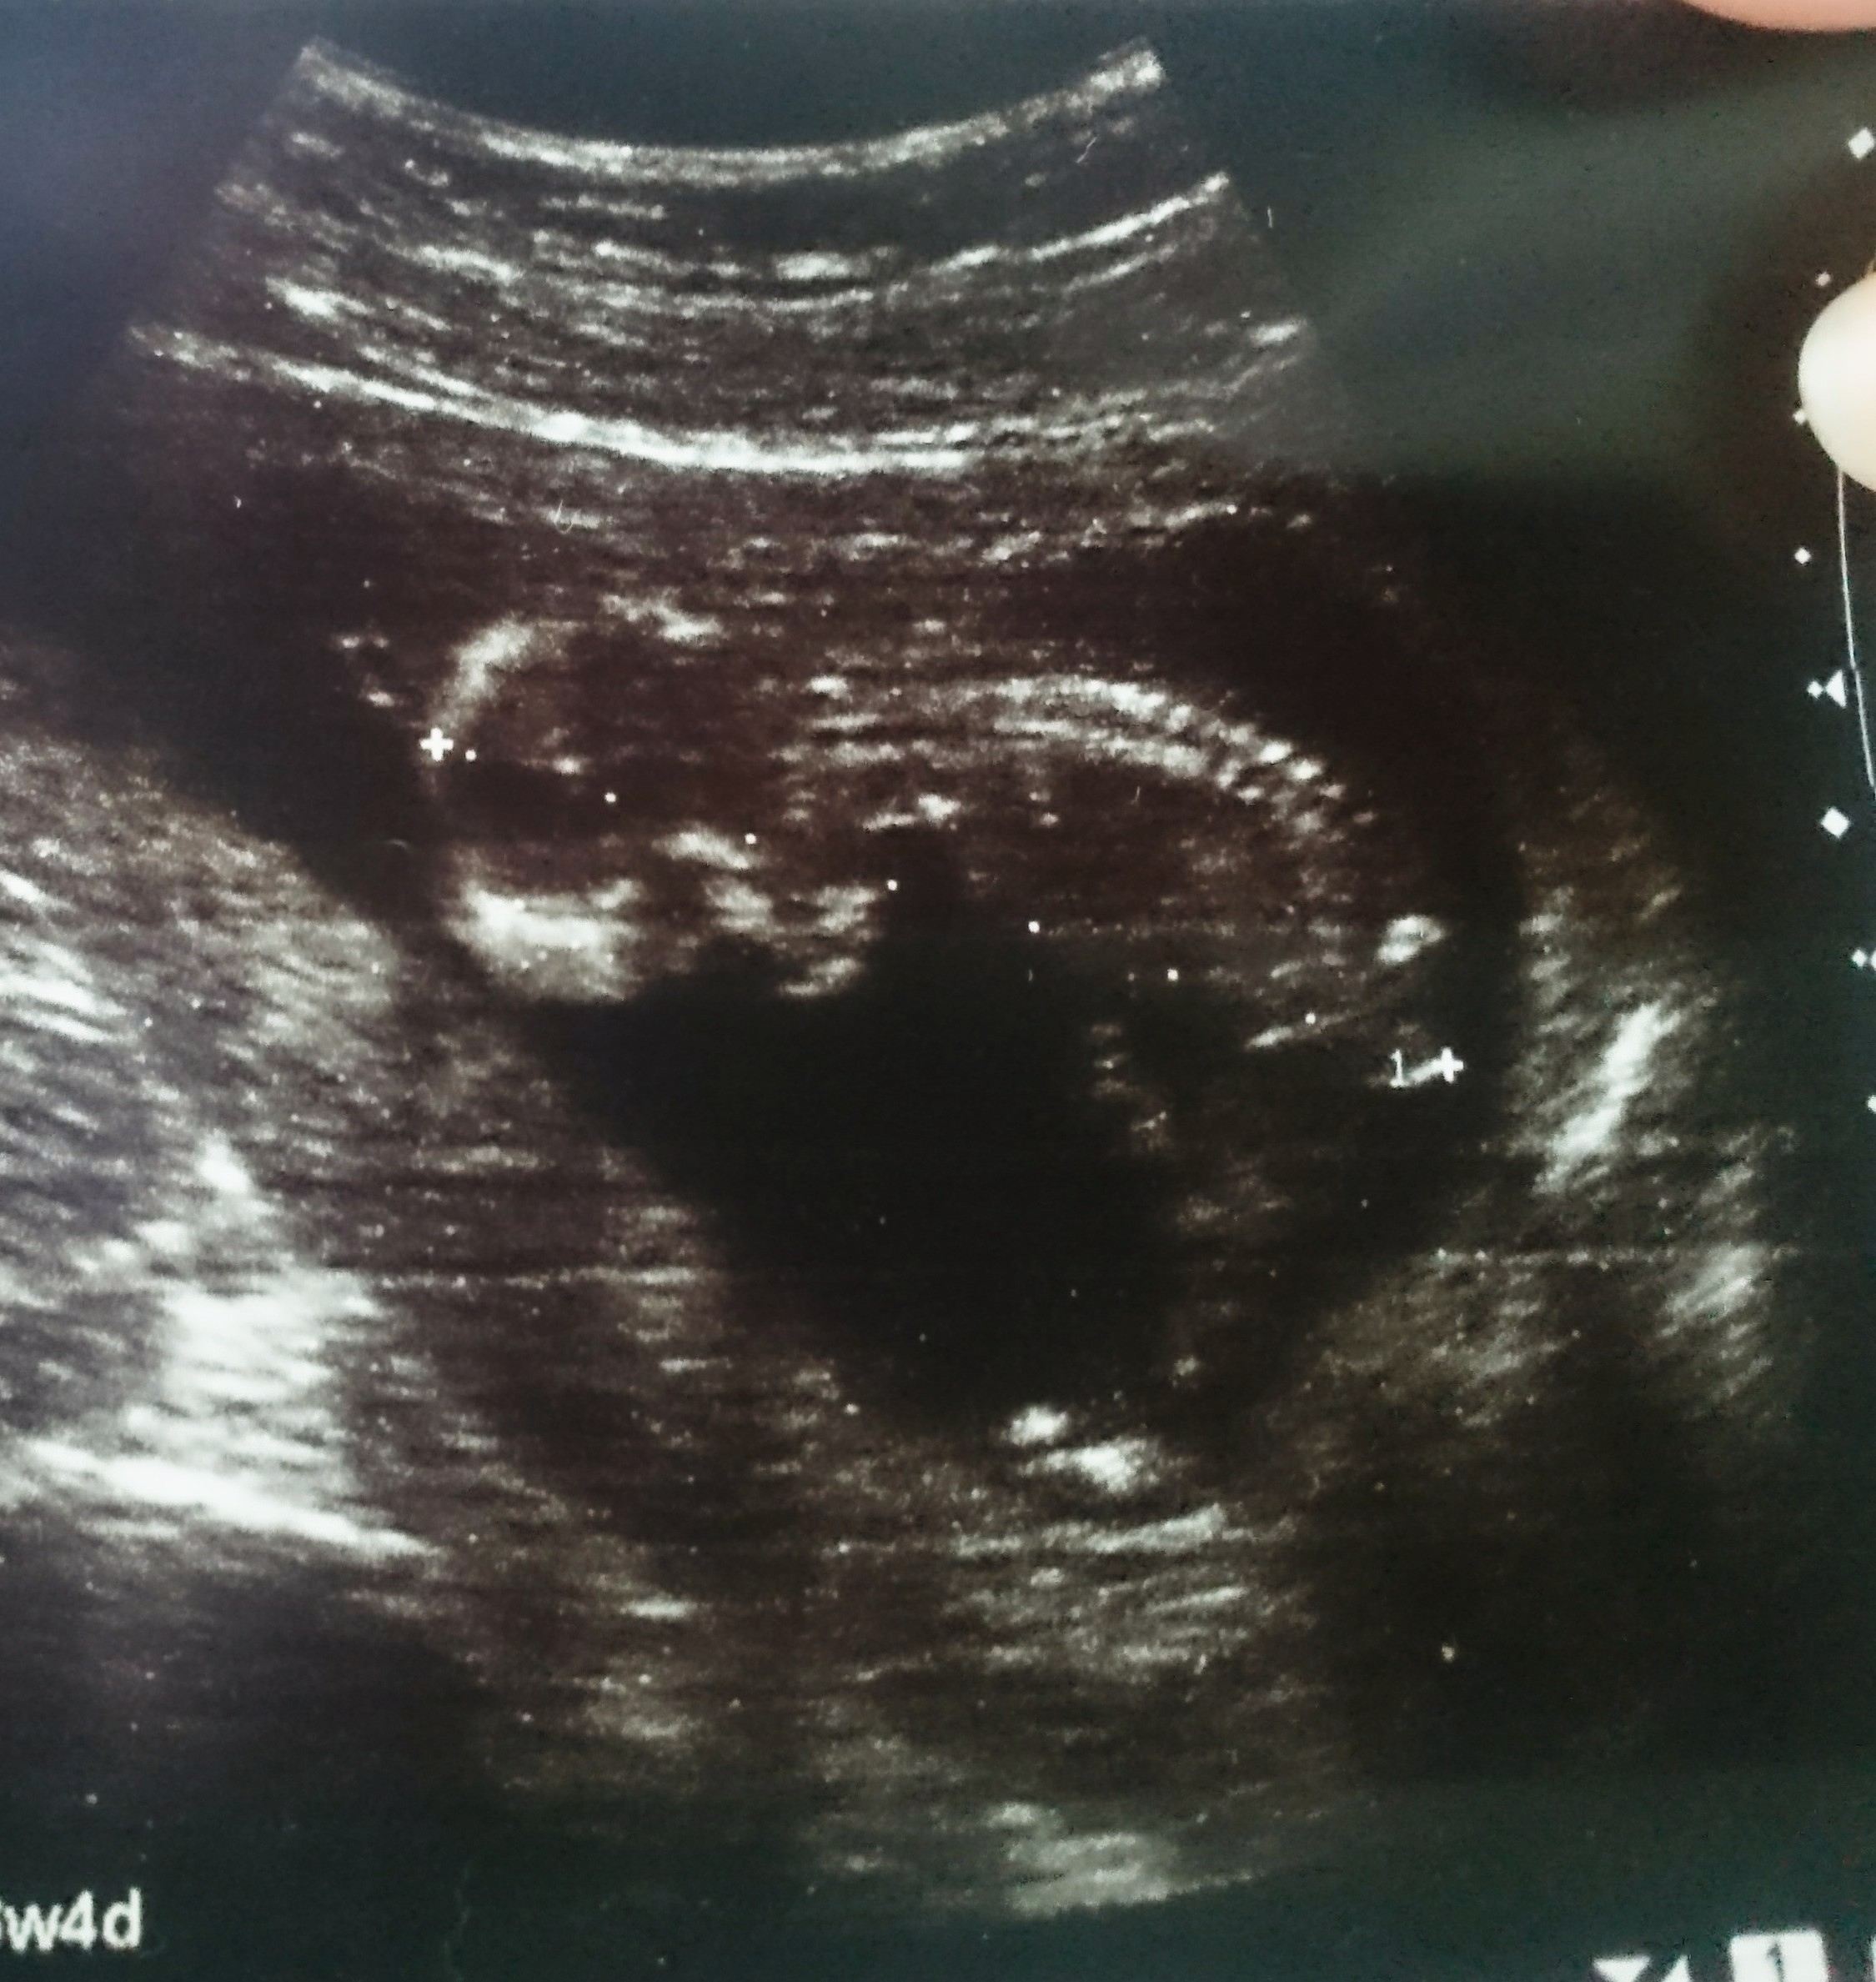

Usg chłopak czy dziewczynka

Witam w 19 tygodniu ciąży dowiedziałam się ze będę miała dziewczynkę w 20 tyg okazało się jednak , że to chłopak. Sama już nie wiem bo na jednym usg widać na pewno dziewuche a na drugim chłopca. Może to pempowina ?? Może ktoś mi pomoże rozwiązać ta zagadkę

Załączniki

• 4A8F5FF1-76CA-4DE0-AC12-5EDF08E820F2.jpg

4A8F5FF1-76CA-4DE0-AC12-5EDF08E820F2.jpg

596,4 KB · Wyświetleń: 44 131